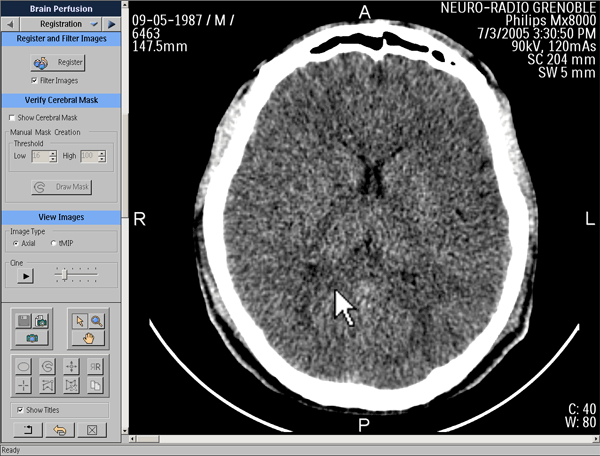

Post-traitement

Recalage des images

Vérification du masque